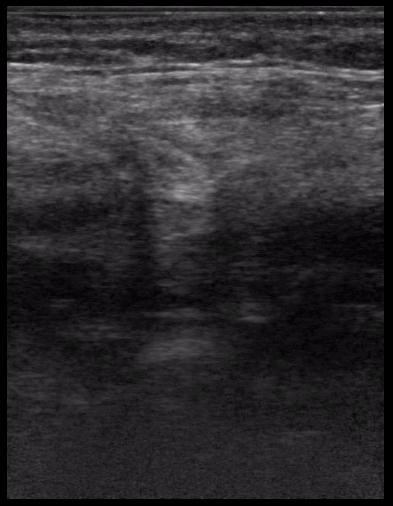

спустя 8 мес. после операции